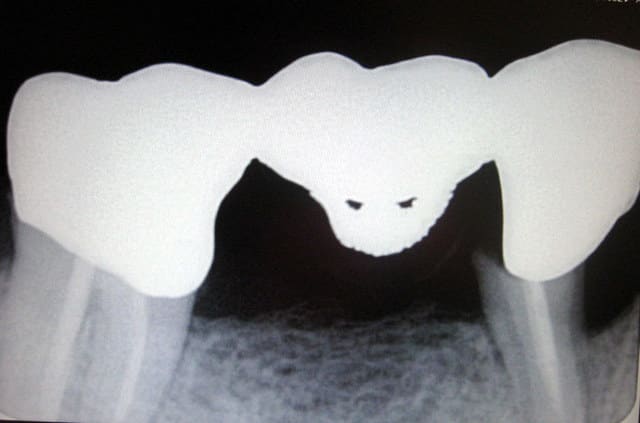

Sur un nouveau patient. Il fait une drôle de tête ce bridge. ;-)

roumette sur ta 1ère radio dégomme vite ces space-invaders, sinon tu vas te faire bouffer !!

> Sur un nouveau patient. Il fait une drôle de tête ce bridge. ;-)

Le pilier mésial aussi!!!